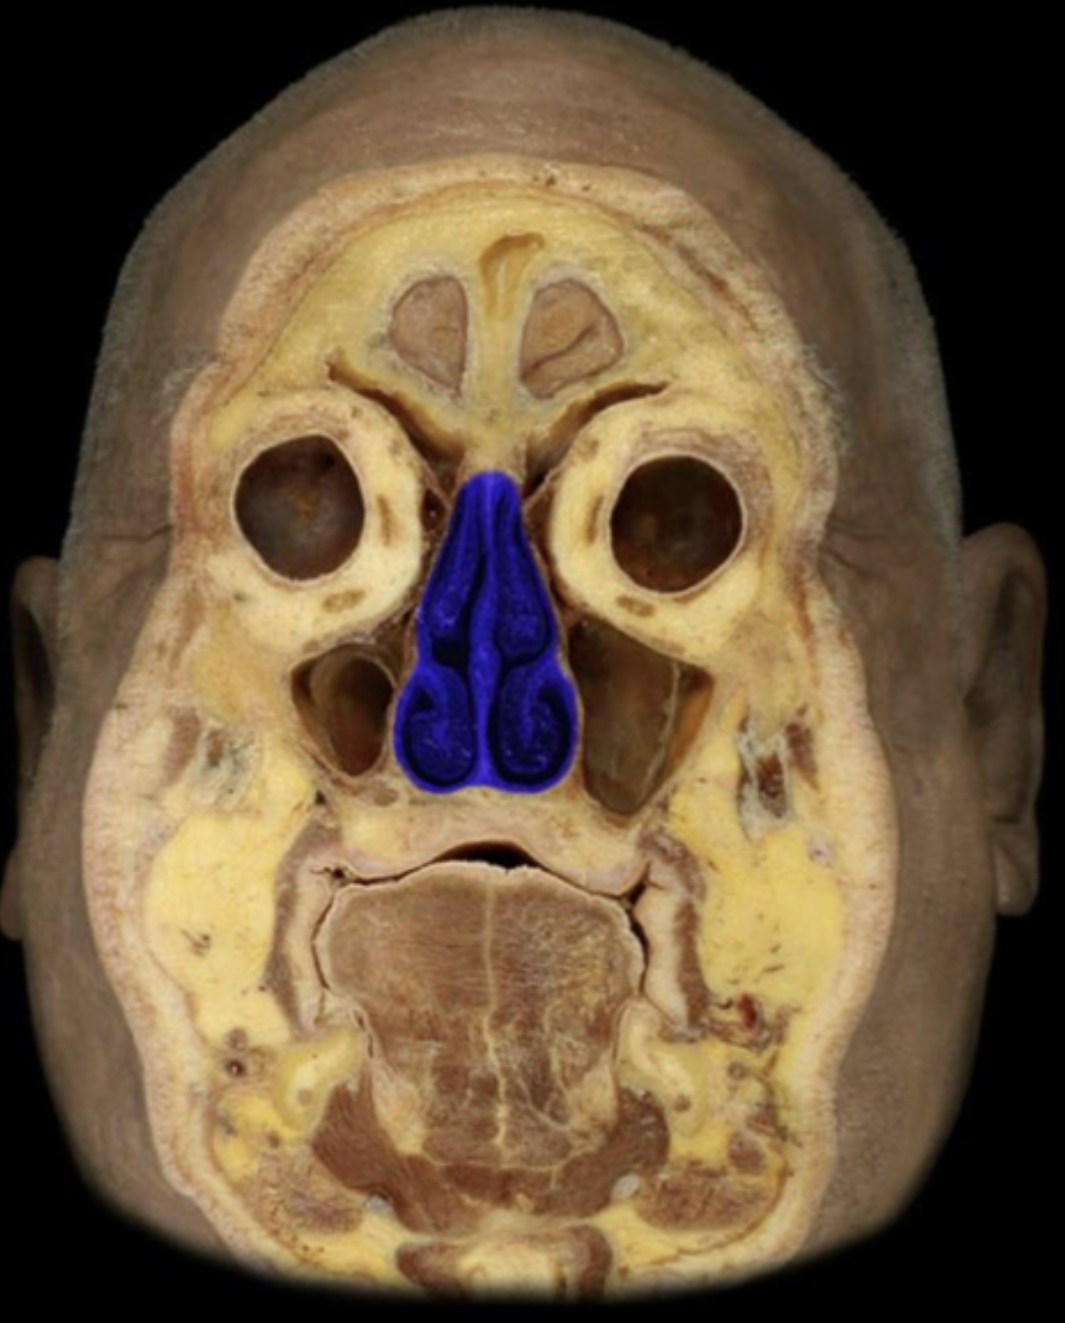

What structure is highlighted in blue?

Nasal cavity